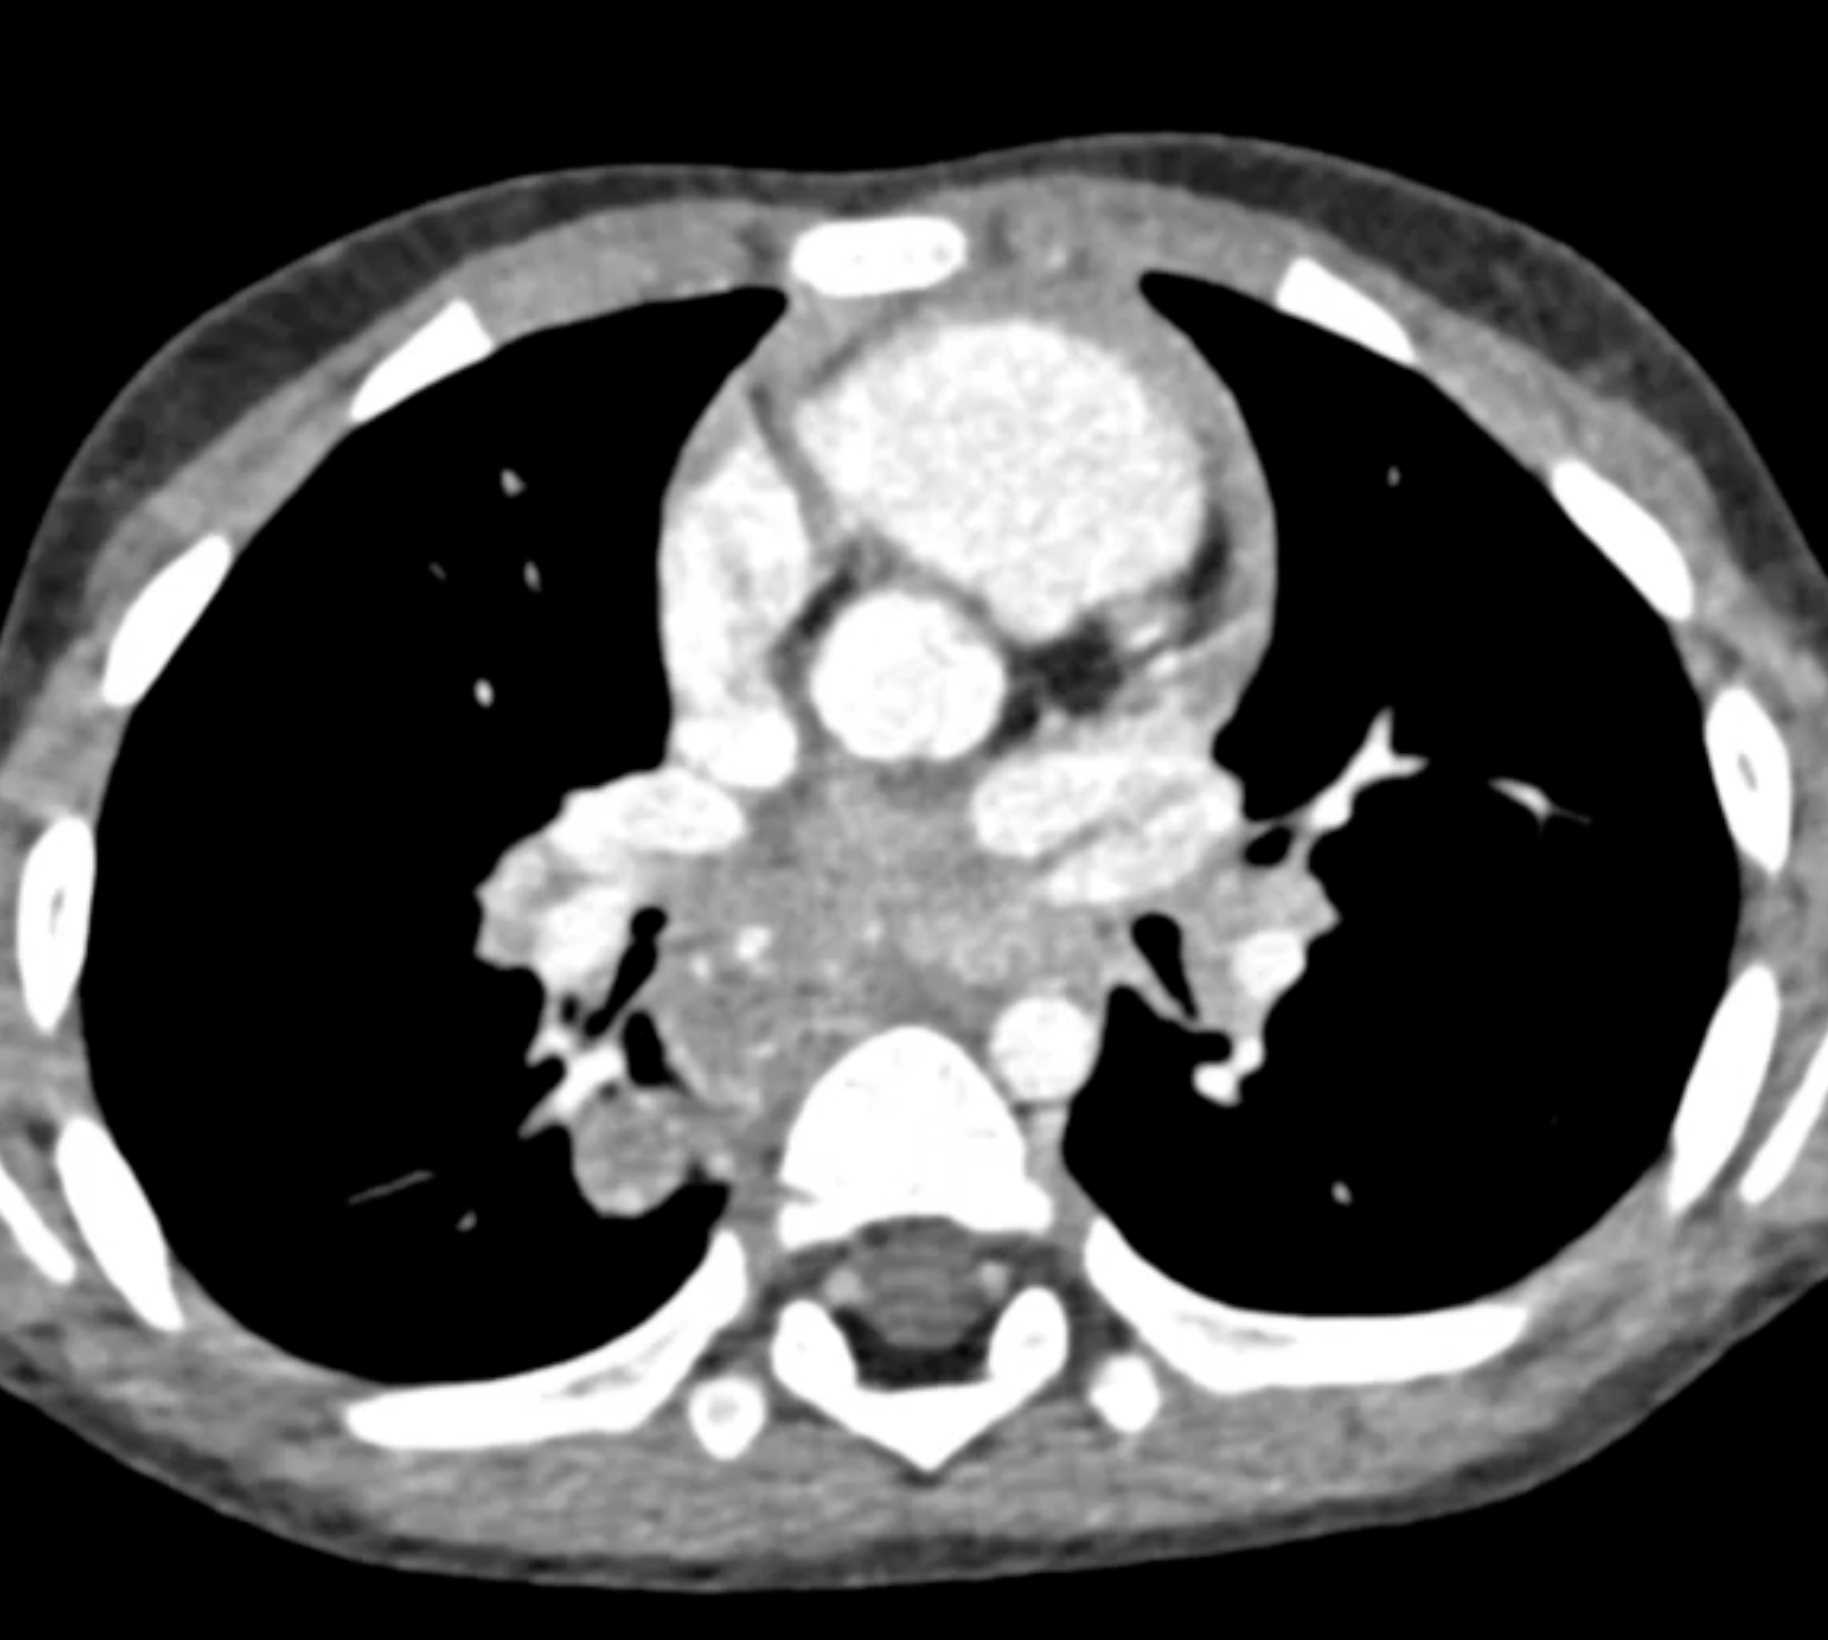

Histoplasmosis and Normal Thymus